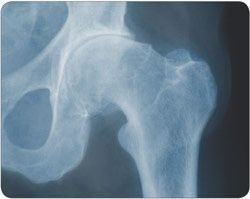

Neue Mobilität bei Arthrose durch defektorientierten Gelenkersatz

In Deutschland werden jährlich ca. 150.000 Knie-, ca. 200.000 Hüft- und ca. 10.000 Schultergelenke durch ein Kunstgelenk ersetzt. Die steigenden Implantationszahlen sind u.a. auf die stetig alternde Bevölkerung zurück zu führen.